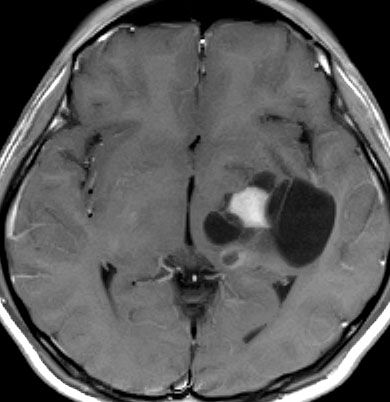

Tourette syndrome(音声と行動のチック,不随意運動)で発症した男児です。石灰化もありのう胞も伴う大脳基底核gangliocytoma grade 1で,摘出にはリスクがあると判断して46グレイ23分割の定位放射線治療をしました。しかし治療抵抗性で増大したために,上側頭溝からの経路で腫瘍を摘出(右の画像)しました。それ以来13年が経ちますが再発はありません。グレード1の神経節細胞腫は放射線治療抵抗性のものが多いと考えた方がいいし,より大きな線量を使用しても同じ結果なのでしょう。

脳幹部から発生した退形成性神経節膠腫 grade 3

軽い右顔面神経麻痺で発症した小児で,右上下肢の軽度の失調症もありました。脳幹部(橋)の右背側から発生した腫瘍で,軽度の閉塞性水頭症を合併しています。左はT2強調画像で,橋の右側ににじむような浸潤像と浮腫があります。腫瘍は小嚢胞を形成してT2強調画像で実質は等信号です。真ん中の画像はCISS画像で橋が腫大しているのがよくわかります。右側はガドリニウム増強像で,全体が増強されてまだらな増強所見となっています。正中後頭下開頭で全摘出 gross total removal して,局所放射線治療とtemozolomide, cisplatine, etoposide, gleevec, hydoreaなどの化学療法を行いましたが,手術後4ヶ月で激しい播種再発を来しました。